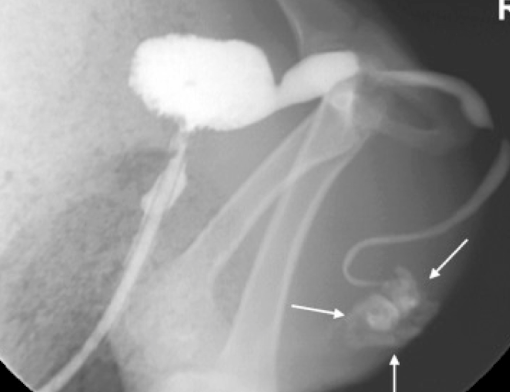

Stones may lie more proximally (need ultrasound/rads/contrast beforehand)

What makes retrograde catheterization difficult in these species?

Inability to exteriorize penis

Sigmoid flexure

Urethral diverticulum (especially in cattle)